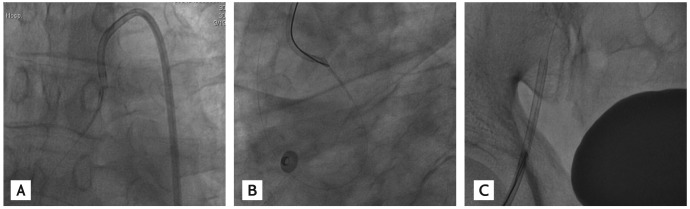

Figure 5

(A) A 2.5 × 28-mm Xience stent (Abbott Vascular) was implanted in the proximal left circumflex artery. (B) A 3.0 × 28-mm Xience stent was implanted at the total occluded proximal left anterior descending artery.